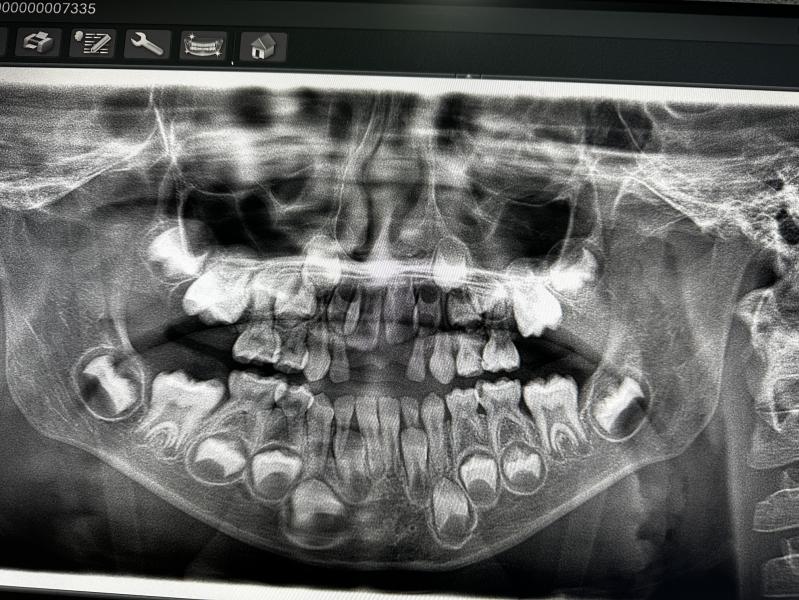

Сходи мы к стоматологу, дал посмотреть и сделать снимок . Но дальше я уговаривать не стала , это только первый этап .

2 зуба нужно лечить по любому , 3 зуб под вопросом .